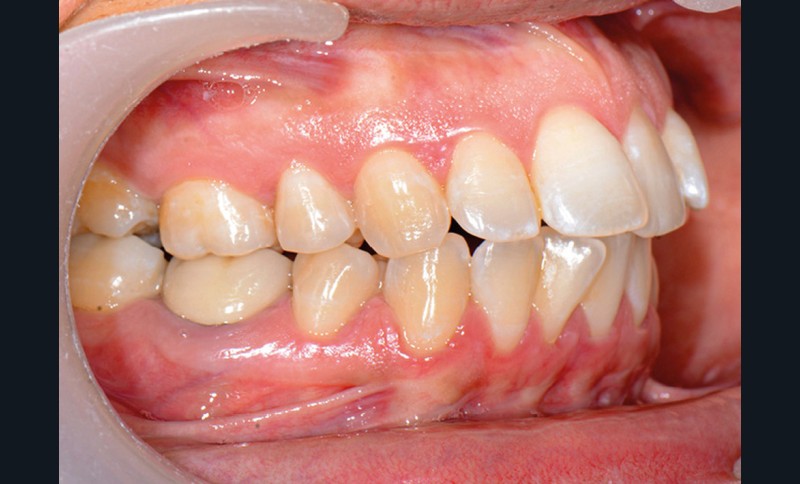

C’est précisément le cas de cette patiente de 33 ans qui présente une classe II squelettique par rétrognathie mandibulaire sur un schéma vertical hyperdivergent associée à une classe II/1 dentaire avec DDA par excès et biproalvéolie. Son profil est convexe, cis-frontal et, sur le plan fonctionnel, on peut observer une dysfonction linguale et une incompétence labiale au repos. Il en résulte une contracture des muscles de la sphère péri-orale lèvres jointes. La formule dentaire n’est pas complète puisque les quatre deuxièmes prémolaires ont été extraites lors d’un premier traitement orthodontique et qu’il y a également agénésie des troisièmes molaires 18 et 38 (fig 1 à 11).